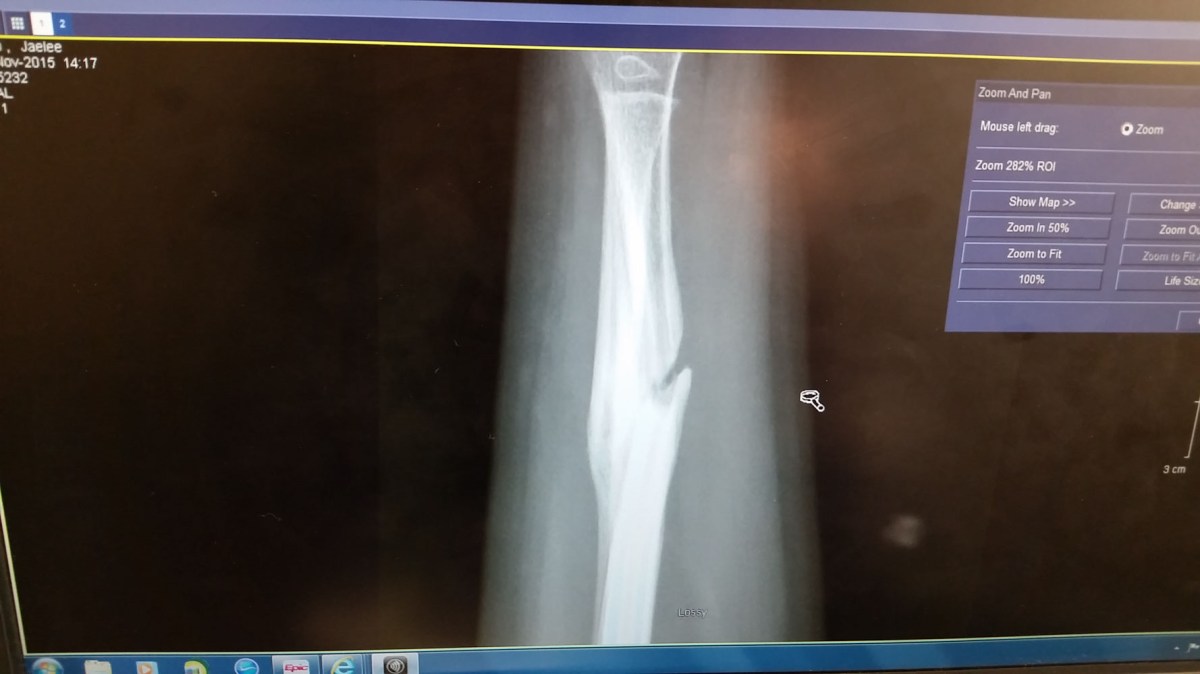

The took another xray to see how the bone was healing. It still had a long way to go so the Dr. had us put a brace on her and wanted her to wear that for another 4 weeks.